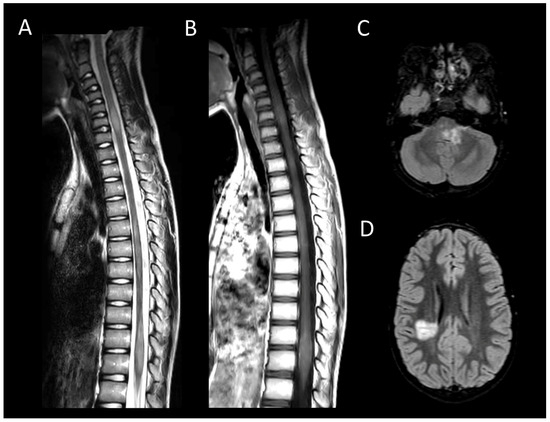

Neurosarcoidosis

Anti-GFAP Encephalomyelitis

Autoimmune Myelitis